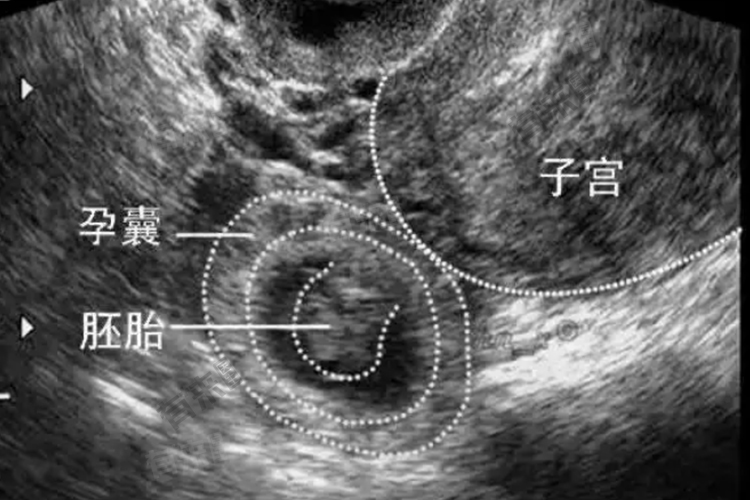

- 在孕6周时,胚胎已经经历了显著的发育变化,此时,胚胎的头部、躯干和四肢开始形成,但尚未分化出明显的器官结构。心脏也开始跳动,虽然速度较快且力量微弱,但是胎儿生命活动的重要标志。此外,胚胎的神经系统也在迅速发展,为后续的器官发育和功能完善奠定基础。